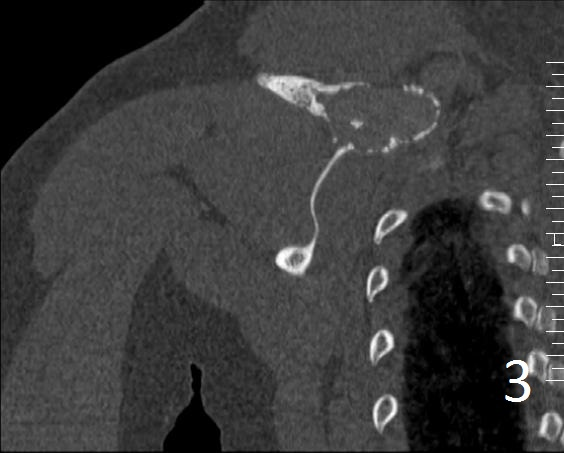

• Useful to determine the extent of the lesion as well as ground glass appearance (Fig. 2-3)

• Well defined borders

• Possible endosteal scalloping lesion

• Areas of mineralization within.

Fig. 3. Coronal CT of the right shoulder shows a expansile lytic lesion with cortical bone expansion.